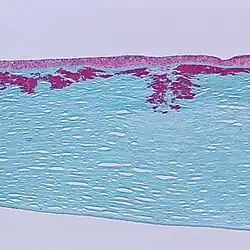

Reis-Bücklers corneal dystrophy. Light microscopy of cornea showing characteristic red stained deposits of mutated TGFBI protein in the superficial corneal stroma. Masson's trichrome stain.

Mutations of the gene cause several forms of corneal dystrophies.[7][8]